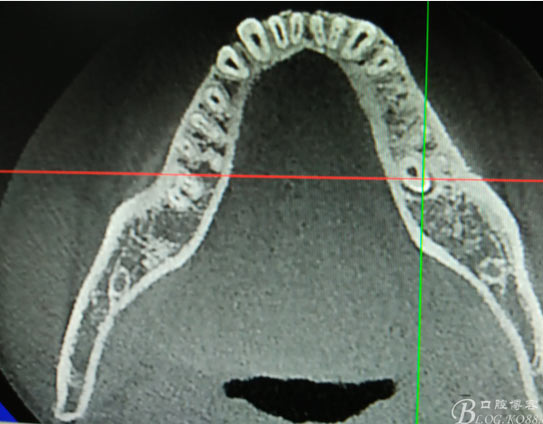

患者、盧xx、男、19歲。主訴:左側(cè)下頜乳磨牙未脫落,要求檢查。??茩z查:左側(cè)下頜第二乳磨牙有充填物。無松動,全景片檢查。35移位至36、37之間。頰舌側(cè)均不能觸及隆起。CBCT檢查:35位于36、37的舌側(cè)。表面骨質(zhì)約2mm左右。35完全骨埋伏,36的遠(yuǎn)中牙根疑是吸收。建議35暫觀察。置留不取?;颊咭蟀纬龘?dān)心壓迫36牙根或者發(fā)生囊性變。術(shù)前簽手術(shù)同意書。

圖1.術(shù)前的全景片影像檢查,35移位至36、37之間。